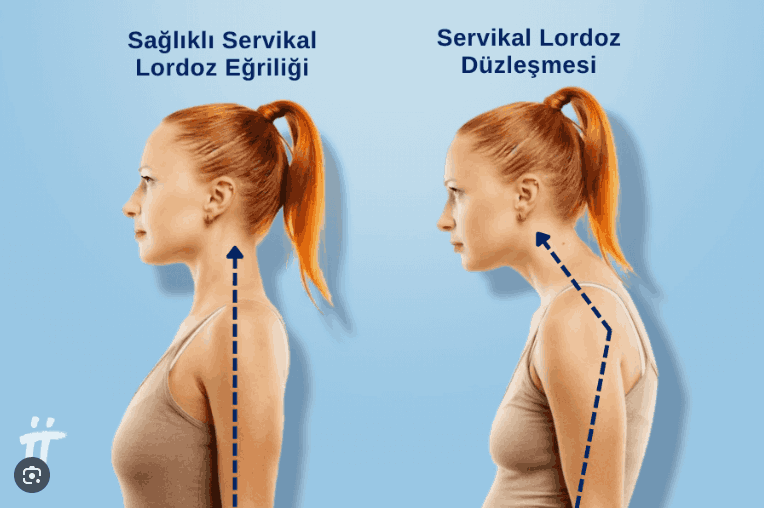

Sorun şuymuş : Boyun Düzleşmesi

Bunun olayı da, boyundaki omurların normalde olması gereken şekilde olmaması gereken şekle dönmesi ve bunun neticesinde sinirlere vs baskı uygulayıp ağrılar, sancılar ve ileri seviyelerde duyu kaybına sebeb olmasıymış.

O da bu resimdeki oluyor.

Şu resimdelerden soldaki gibi olmak lazım, sağdaki zürafaya benziyor :D